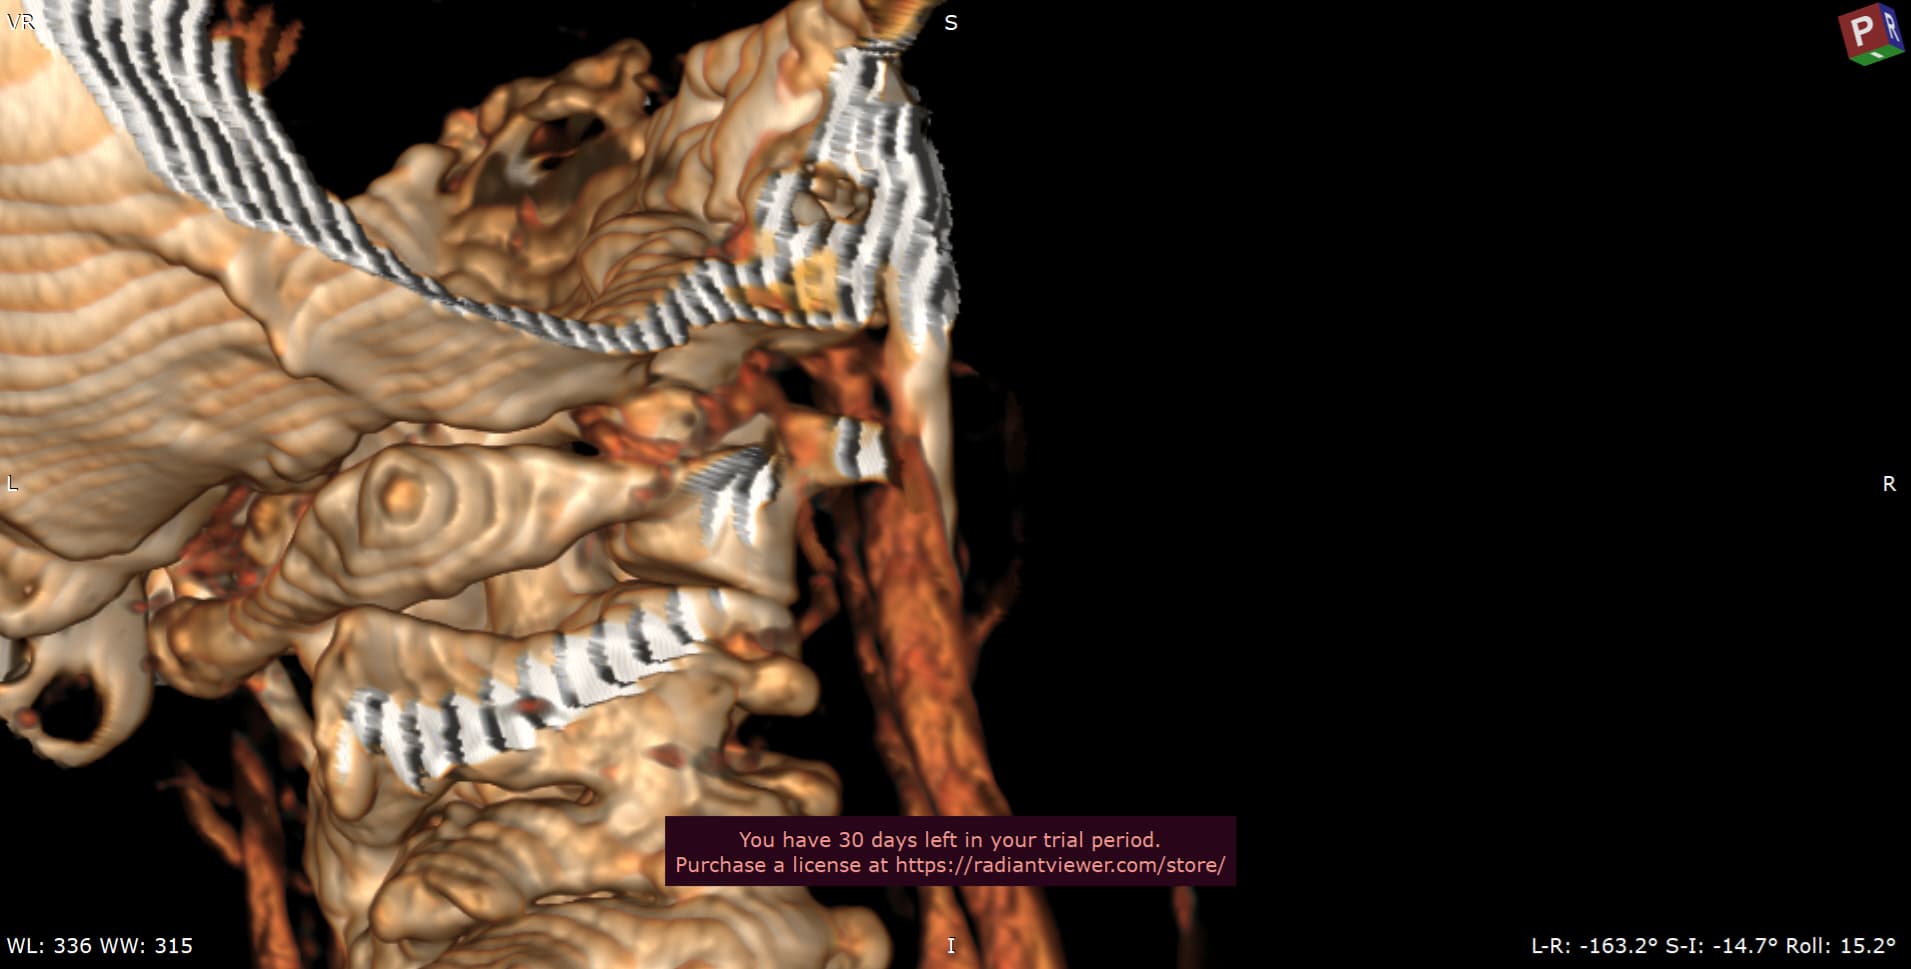

Please do a CT VENOGRAM of the brain and cervical spine with contrast. Please do a 3D reconstruction to show styloids. Please also measure the styloids.

Patient with symptoms of intracranial hypertension (pseudotumor cerebri) compatible with compression of the internal jugular vein at the transverse process of atlas (C1) or styloid process. Please do the scan in neutral.

Please make sure the CT Scan is capture while the contrast is in the internal jugular vein. This patient is suspected of having significant compression of the internal jugular vein(s) between the styloid bone and/or atlas. This is not a CT angiogram order it is a venogram. Surgical decisions will be made based on this scan.